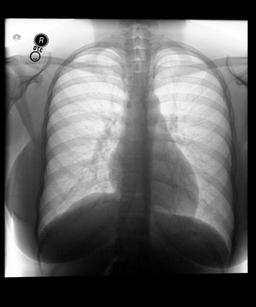

We found that many lateral acquisitions in the dataset were unexpectedly labelled as frontal (Figure 7(a)). Some images contained only noise (Figure 7(b)), non-human samples (Figures 7(d) and 7(e)) or incorrect anatomy (Figure 7(g)). Often, acquisitions with an incomplete field of view (FOV) (i.e., the lungs are not completely visible) were repeated (Figure 7(c)). Lastly, post-processed images were detected by the algorithm such as contrast-enhanced scans (Figure 7(i)) that are not often used for diagnostic purposes in clinical practice.

Curation of imaging datasets

CXR datasets [36] often contain multiple image acquisitions in a single visit due to data quality issues such as a limited field-of-view or scanning the wrong body part (Figure A.7). Unlike [9, 32, 81], we conduct curation to choose higher quality images among the potential candidates instead of performing a random selection. For this step, a separate BioViL-T is trained on ‘clean’ studies with single acquisitions and later used in a zero-shot setting to detect out-of-distribution samples [26, 27] arising from the re-imaging process. The candidate is selected as follows: for a margin . This approach is applied to enhance the quality of the temporal classification dataset given its limited size.